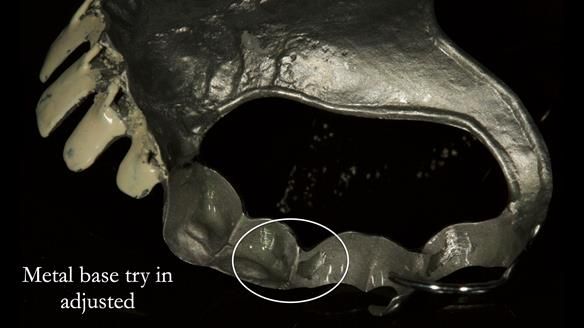

Keith’s case was one of the most challenging and rewarding cases I’ve treated this year. This 64 year old man presented with ill-fitting acrylic partial dentures that lacked stability, retention, and aesthetics. They constantly broke. He had lost the upper front teeth in a road traffic accident in his early 20s. The unopposed teeth had erupted, taking up space. After careful planning, we made a durable, metal-based upper partial denture/splint to address his dental concerns. He loved the outcome.

1. Denture design: A custom cobalt-chromium framework was Scandinavian-designed to maximise stability, protect the remaining teeth, and allow for future additions if needed.

Keith’s denture incorporated a Duracetal shell clasp on upper right first premolar (Myerson), which are designed to be virtually visible, providing a more aesthetic solution while enhancing patient comfort. The Scandinavian-inspired approach, based in modern removable prosthodontic techniques, ensured the denture was not only durable but also visually pleasing. Additionally, the design was carefully planned to allow for future modifications, ensuring that if Keith loses additional teeth, the denture can be adapted rather than replaced entirely.